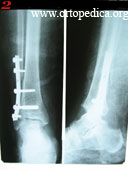

Пример №10 МОС лодыжек